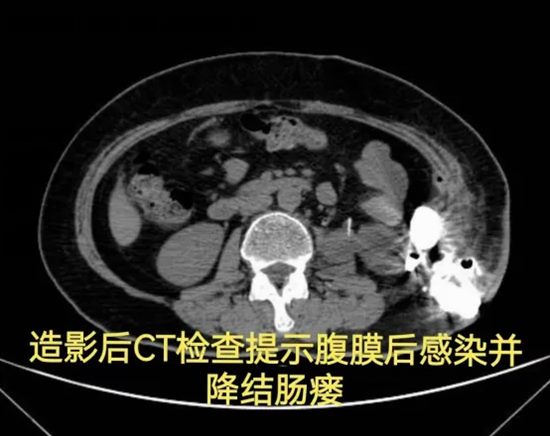

病情简述:56岁女性,两次腹膜后手术后出现降结肠瘘。

诊疗破局:按传统疗法,需先做结肠造口(挂粪袋),等半年后再做二次手术还纳。为减轻患者痛苦,团队制定“清创、控感、一期修复”三步法,实施腹腔镜下瘘切除+一期结肠端端吻合术。术后一周患者正常进食,免去了半年造口之苦。